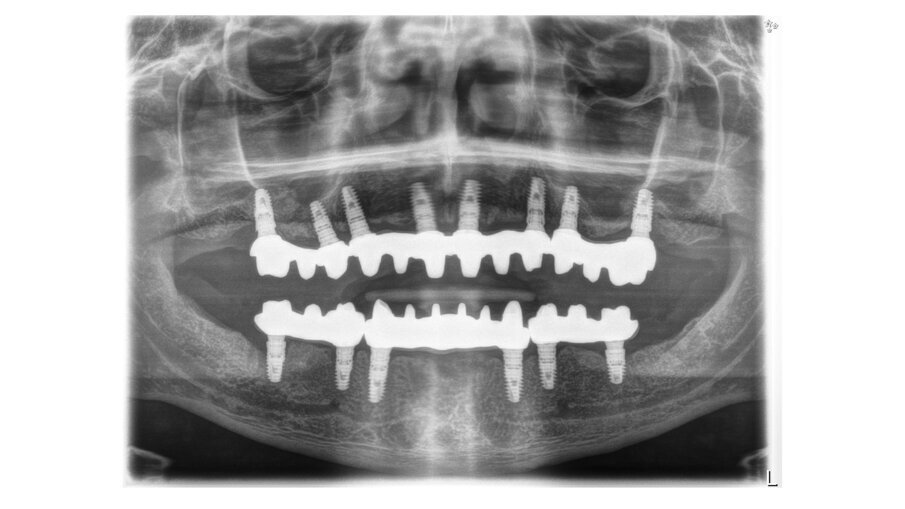

In this case, a patient presented with extremely atrophic bone in the mandible, with four short implants placed between the dental nerve foramen (Figs, 10a, 10b). After some time, patients wearing this kind of restoration with prefabricated teeth, their muscle activity increase considerably, which very often leads to fracture or debonding of the prefabricated teeth (Fig. 12). A combination of a rigid metal structure over the telescopic bar and a thimble structure made of PEEK (Fig. 13, 14) works as base for the final restorations. These were milled out of a BRILLIANT Crios disc either as single tooth units or bridges and cemented on the thimble structure (Figs. 15-17). Using BRILLIANT Crios instead of prefabricated teeth, we can increase the strength of the restoration, have good aesthetics and keep the weight low for this kind of prosthesis.

Figs. 10a and 10b : Patient with extremely atrophic bone in the mandible with four short implants placed between the dental nerve foramen